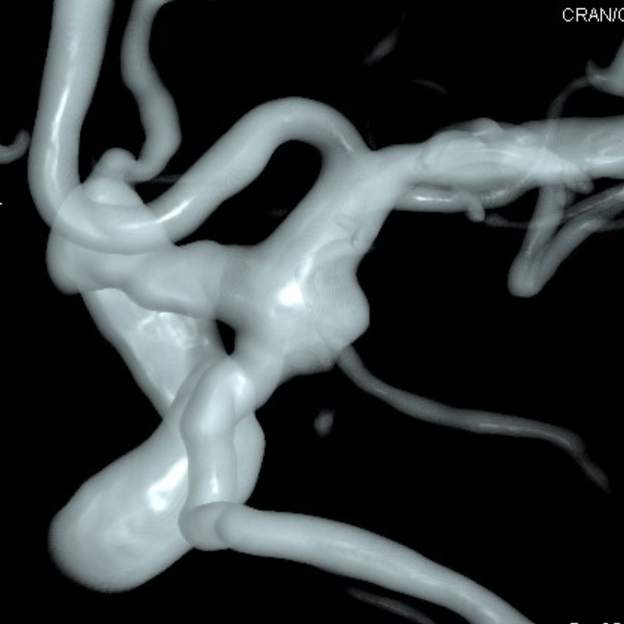

动脉瘤经过多年修炼,形态奇葩,大动脉瘤上长着小动脉瘤,小动脉瘤上长着微小动脉瘤,还累及粗大的胚胎型大脑后动脉,经过一期单纯栓塞,消除了出血风险,老人家顺利出院康复。

近日,老人家恢复了差不多了,为了防治日后宽颈的脑动脉瘤复发,还需要稍微进行一下修修补补,减少血流对薄弱的脑动脉瘤的冲击,那就需要再简单加固一下。

这个加固的材料呢,放进血管后,慢慢会被自己的内皮细胞覆盖,变成自己身体的一部分,还能防止动脉瘤复发,是一个非常好的装备。

装备虽好,那还的找靠谱的医生给安装进去吧。今日,我们顺利为老人家在病变部位的血管植入了血流导向装置,手术顺利。然而,不是每一个破裂的脑动脉瘤患者像老人家一样这么幸运,能够有机会赶到医院,得到及时的治疗……